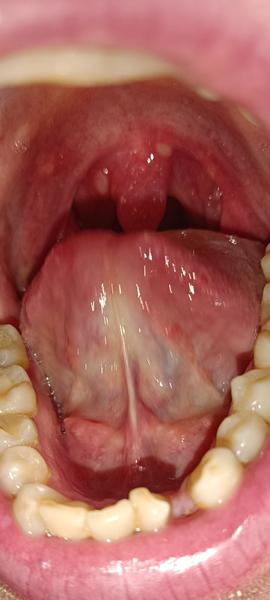

Ahojte vysypali sa mi takto hrdlo ledva prehltam a som stoho nervozny ,teplota ani nic ine mi neni ,dakujem co mi pomoze

@tetapetra toto je hnisava angína, on má len afty

@minenkak začiatok môže vyzerať aj tak, som presne ten typ, ktorý máva len hnisavé angíny

@tetapetra tak uz ma hrdlo zacalo bolet 4 dni dozadu a zrazu toto ,ale replota nic ani kasel. Ani nevim co ,no mozno angina moznonlen tie afty alebonco to je

@kondrs máš afty ,kup tantum verde sprej alebo kloktaj slanú vodu a bude horúčka tak hnisava angína a Bkomplex som zabudla

@kondrs kúp glimbax, ak si v takom štádiu,tam by som radšej šla k lekárovi kvôli ATB

@kondrs je aktualne velmi rozsireny streptokok s atypickym priebehom. Zasla by som na vyter. Pre istotu. Je to mrcha